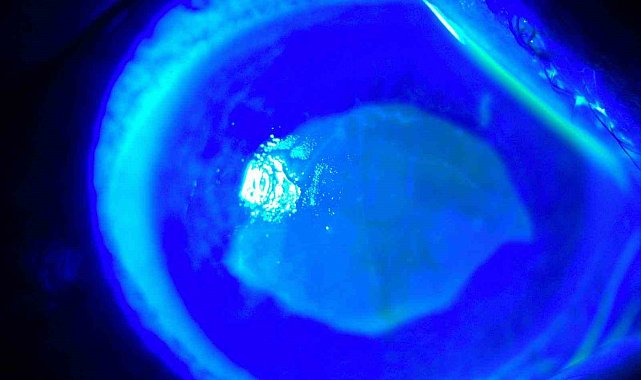

Kocaeli'nde yaşayan 52 yaşında kadın, iddiaya göre uzağı görememesi sebebiyle kullandığı gözlükten kurtulmak için yaklaşık 7 ay önce kırlangıç otunun suyunu gözlerine damlattı ve bir anda göremez hale geldi. Önce gözlerinde yanma, batma hisseden ve sonrasında açamaz hale gelen kadın hemen hastaneye koştu. O dönem Kocaeli'nde çalışan Göz Hastalıkları Uzmanı Doç. Dr. Ömer Faruk Yılmaz ve ekibi hastaya müdahale ederken korneanın en dış katmanı olarak ifade edilen kornea epitelinin zarar gördüğü belirlendi. Göze yabancı cisim, kimyasal madde kaçması ya da enfeksiyon durumlarında gözü temizlemek amacıyla uygulanan göz yıkama tedavisi gerçekleştirildi. Yaklaşık 2 haftalık tedavinin ardından hasta sağlığına kavuştu. Doç. Dr. Yılmaz, hastasının yaşadığı süreç ve tedavisine ilişkin bilgi verdi. Yılmaz, hekim önerisi olmadan herhangi bir ürün kullanılmaması gerektiğine dikkat çekerek önemli uyarılarda bulundu. Öte yandan hastanın göz bebeğinin beyazlığı ve göz akının ise kızardığı hali fotoğraf karesine yansıdı.

Hastasına ilişkin bilgi veren Doç. Dr. Ömer Faruk Yılmaz, "52 yaşında bir bayan hastamız, kızının önerisiyle gözlükten kurtulmak için 2 gözüne taze kırlangıç otu suyunu sıkarak damlatmıştı. Kırlangıç otunu sıktığımız zaman sarı bir sıvı akmaktadır. Hastamız o sıvıyı her 2 gözüne damlatmış. İlk aşamada gözünde yanma, batma oluyor, birkaç saat sonra her 2 gözünü açamıyor, tamamen göremez hale geliyor. Bize geldiğinde hastamız 2 gözünü açamaz haldeydi. Göz muayenesinde 2 gözün korneasının tamamen tahrip olduğunu gördük. Korneanın epiteli tamamen soyulduğu için hastamızın gözünde pü şeklinde akıntı mevcuttu. Hasta, 'Acaba göremeyecek miyim, gözüme ne oldu, bu ilacı neden damlattım?' diye sorgulayarak gelmişti" dedi.

"Kırlangıç otu kullandı, hastamız göremez hale geldi eğer tedavi edilmeseydi sonucun ne olacağını bilemiyoruz fakat tedavi sonucunda hastamız iyileşti. Gözlerinin fotoğrafını çektirdim, kırlangıç otunun geçişini gösterdik. Tedavi edilmediği zaman göz içinde belki de körlüğe ulaşabilecek şekilde istenmeyen yan etkilere yol açabilir. Yüzlerce farklı ot olabilir, yanlışlıkla faydalı bir ot damlatacağız diye zararlı bir otu damlatabiliriz. Göze direkt damlatılması steril değildir, göze zarar verebilir, enfeksiyon oluşturabilir. Faydalı bile olsa Sağlık Bakanlığı ruhsat vermeden, ilaç formatına dönüştürmeden, uygun dozajlar ayarlanmadan ve göz hekiminin önerisi olmadan göze herhangi bir bitkisel ilaç damlatılmasını önermiyoruz."